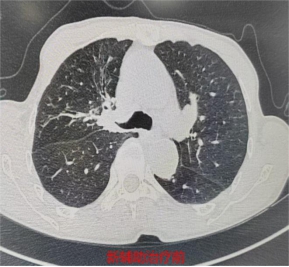

71岁的林先生(化名),4个月前在外院被确诊为右肺上叶肺门处鳞癌(IIIA期),突如其来的重病让全家陷入焦虑,辗转转诊至我院胸心外科寻求进一步治疗。我院胸部肿瘤多学科团队(MDT)首席专家、胸心外科主任医师何昌进牵头,对林先生的病情进行全面研判,结合其高龄、身体基础状况及肿瘤分期,为其量身制定了新辅助治疗联合手术的个体化方案。经过4个周期的新辅助治疗,林先生复查结果显示,肿瘤显著缩小,顺利达到手术指征,为后续手术治疗奠定了坚实基础。

3月10日,胸心外科副主任医师颜海强带领团队为林先生实施了胸腔镜下右肺上叶切除+支气管成形+肺门纵隔淋巴清扫术。术中探查发现,肿瘤紧邻支气管开口,且经新辅助治疗后,肿瘤区域纤维化严重,血管与支气管致密粘连,解剖结构复杂,手术难度极高、风险不小。手术团队沉着应对,凭借精湛的微创操作技巧,精细分离粘连组织,精准辨识并保护重要血管、神经,最终成功将肿瘤完整切除,术中冰冻病理提示支气管残端阴性,确保了手术的根治效果。